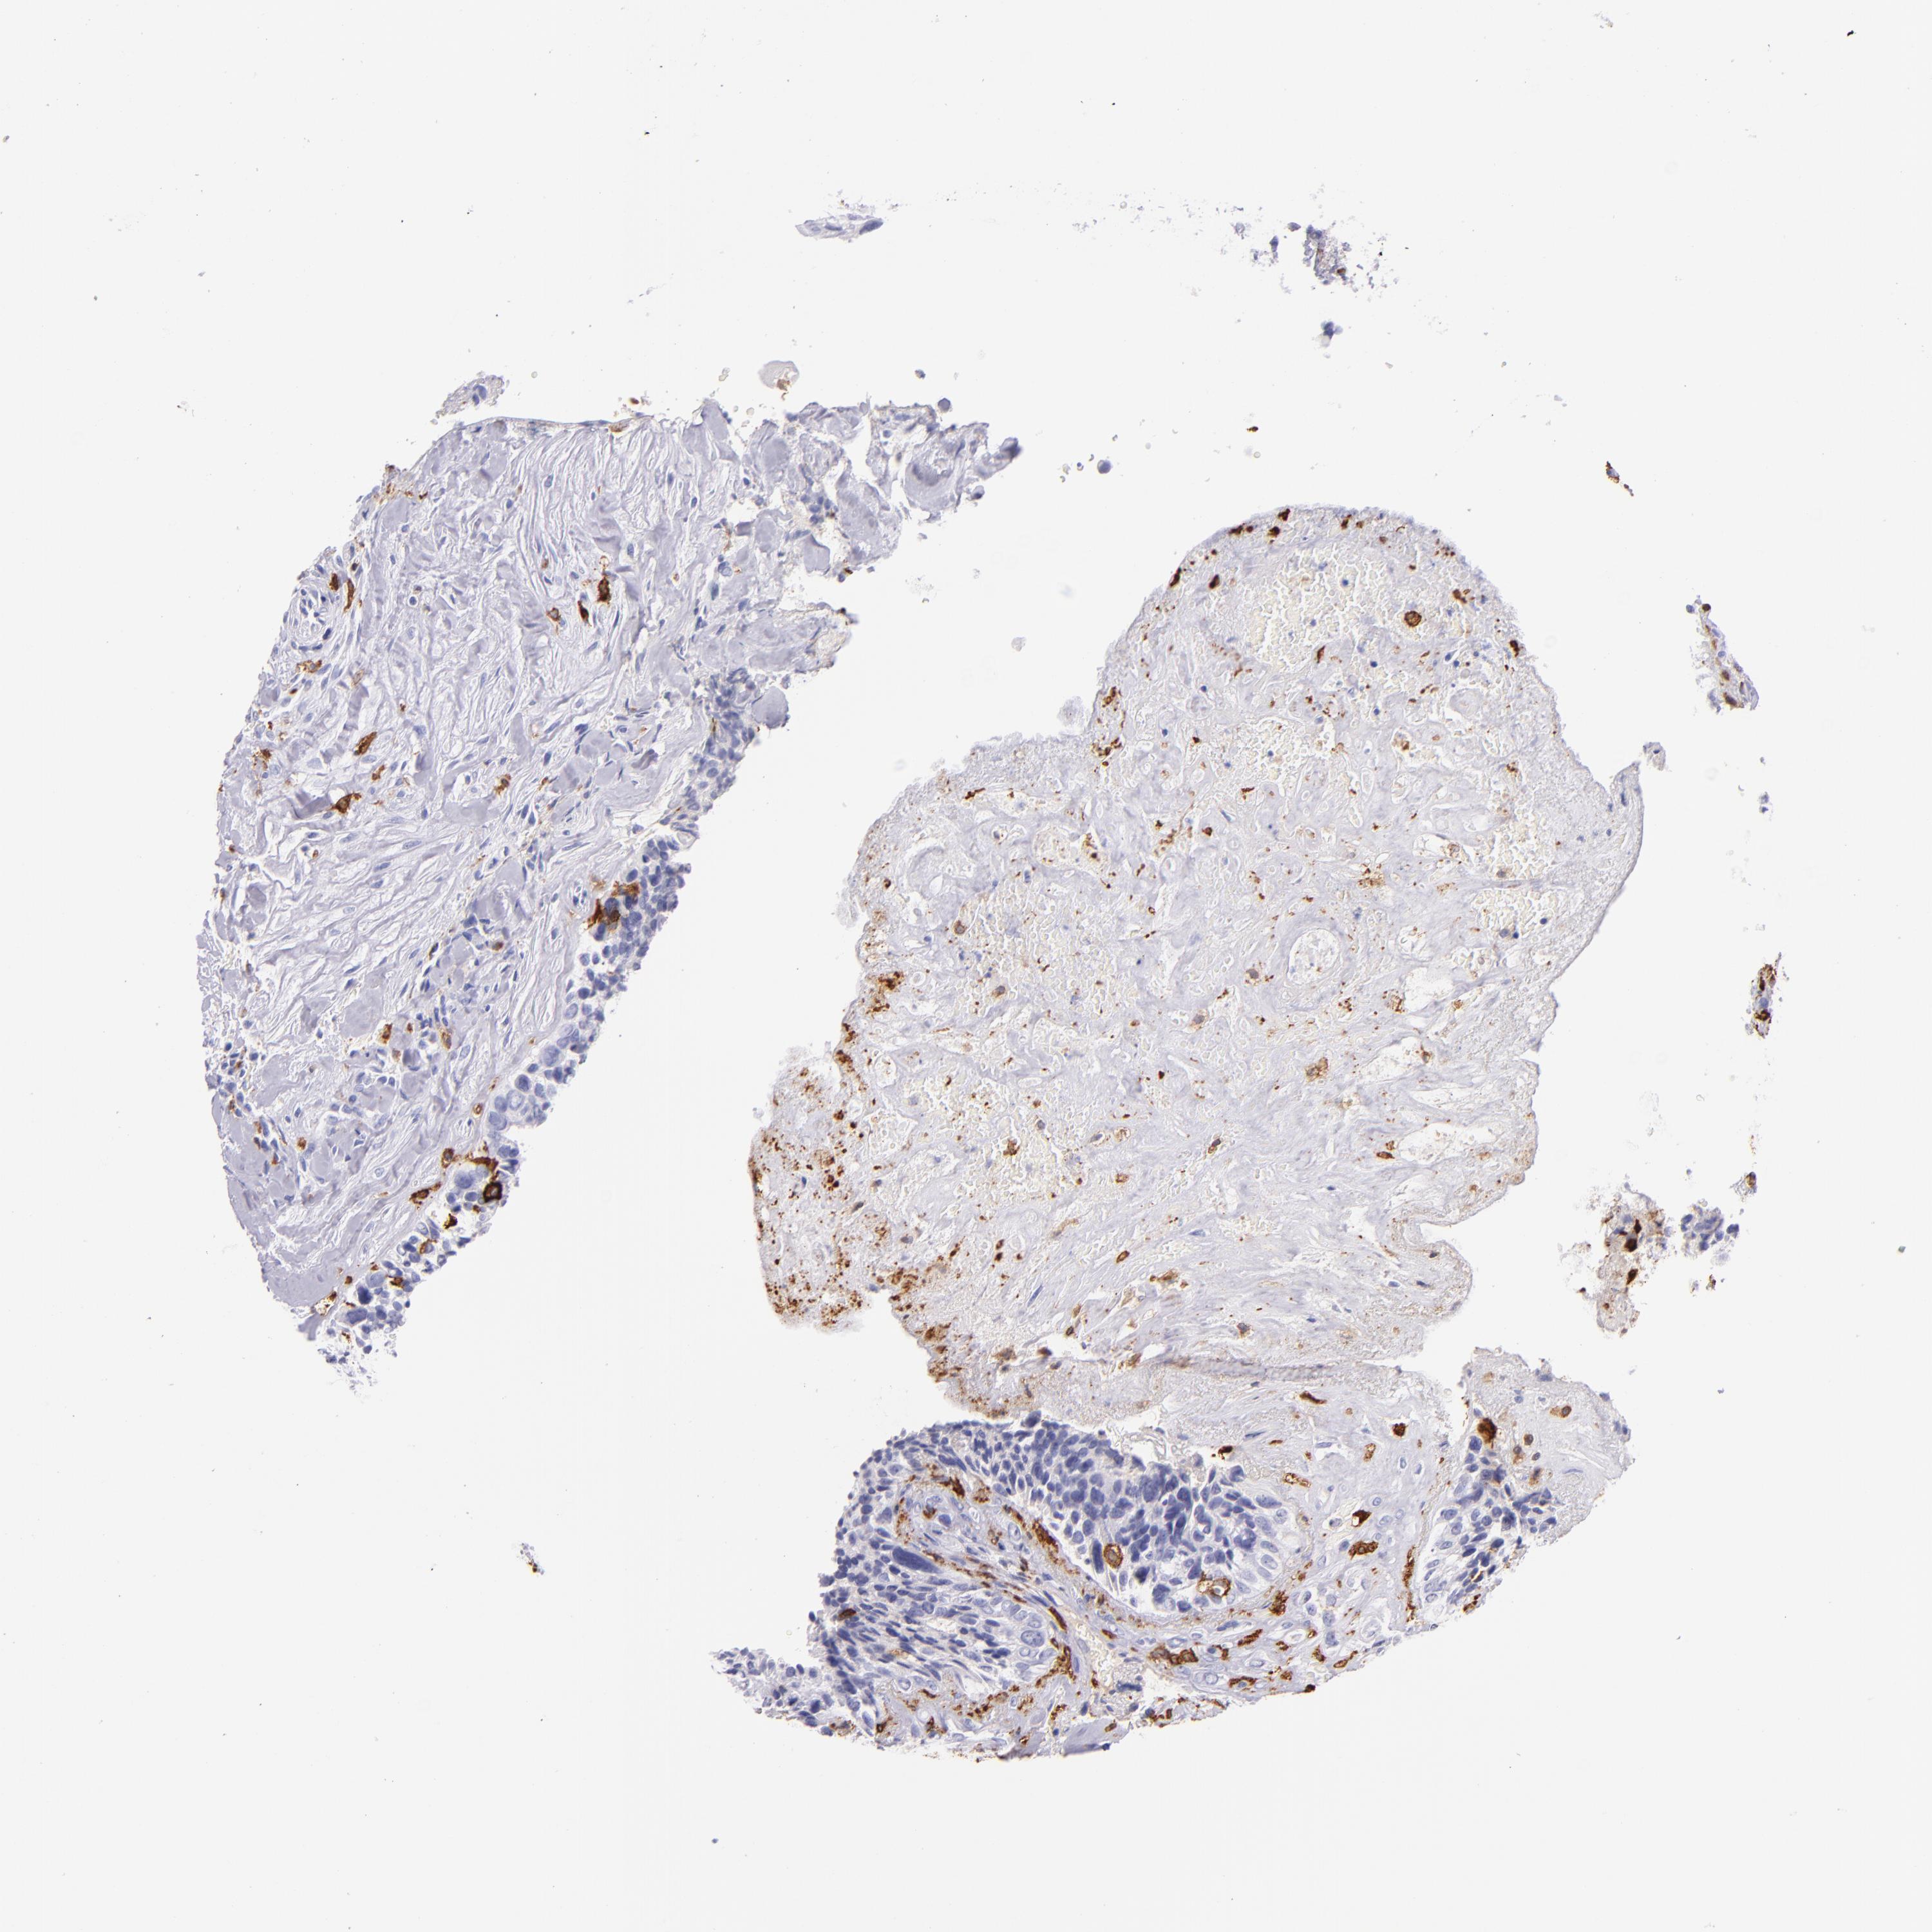

CD163

CANCER BREAST CANCER Show tissue menu

BRCA TCGA BRCA VALIDATION PROTEIN EXPRESSION